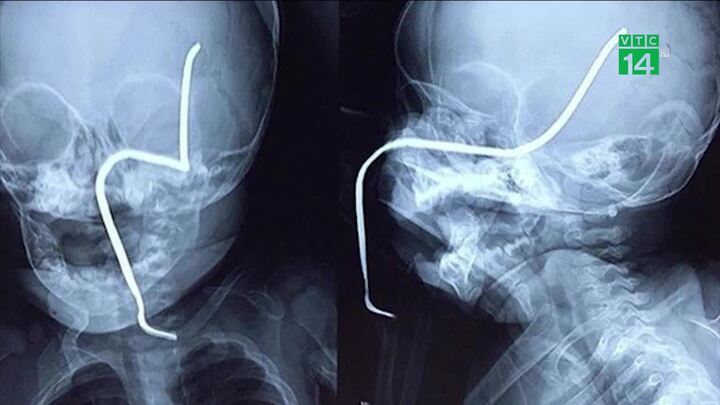

Máy cắt cỏ văng thanh sắt dài khoảng 15 cm nằm dưới cỏ xuyên thẳng vào má trái bé gái 8 tháng tuổi đang chơi gần đó.